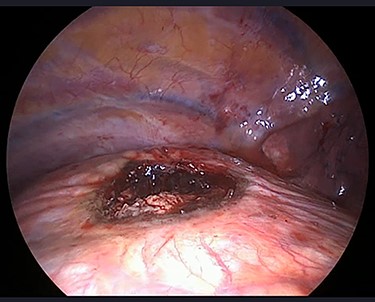

The operation was performed under general anaesthesia with the patient intubated using a double-lumen endotracheal tube. A 4 cm incision was made in the right sixth intercostal space in order to locate the mass. After the insertion of a 10 mm 30-degree thoracoscope, a rounded smooth-surfaced, broad necked mass attached to the right hemidiaphragm was visualized (Fig. 3). The decision to open the diaphragm was made. Further dissection and exploration with an energy device revealed that the mass which was bounded superiorly in the form of a pouch by the diaphragm and had arisen from the liver (Fig. 4). The mass was completely resected with HARMONIC ACE® +7 (Ethicon) after consulting with the hepatobiliary surgeon who felt there was a clear cleavage plane between the mass and liver. The exposed area of liver was covered with Floseal®(Baxter) and TachoSil®(Takeda). The diaphragmatic defect (Fig. 5) was closed in a single layer with 10 simple interrupted silk sutures (Fig. 6). The remainder of the surgery was uncomplicated, and the patient was discharged home on the second postoperative day. Subsequent histology findings reported the mass as benign (accessory) hepatic tissue (Fig. 7).

Diaphragmatic defect was closed in a single layer with simple interrupted stitches.